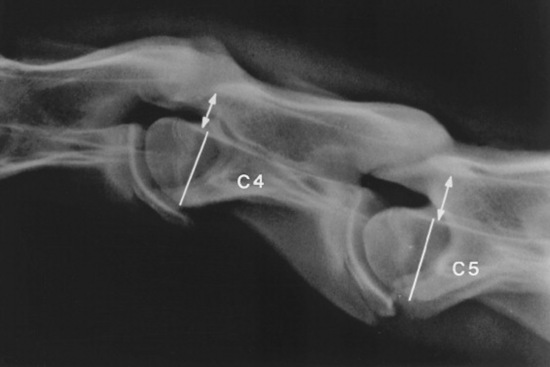

Survey radiographs of the cervical spine are obtained in standing, sedated horses. Cervical radiographs are evaluated by subjective assessment of vertebral malformation and objective determination of vertebral canal diameter.1878 The five categories of cervical malformation subjectively assessed in horses with CVSM are DJD of the articular processes, subluxation between adjacent vertebrae, flare of the caudal physis of the vertebral body, abnormal ossification patterns, and caudal extension of the dorsal laminae1878,1880 (Figs. 35-26 and 35-27). Although the presence of characteristic vertebral malformations supports the diagnosis of CVSM, subjective evaluation of survey radiographs does not reliably discriminate between horses affected and those unaffected by CVSM.1868,1878 DJD of the articular processes of the caudal cervical vertebrae is the most common and severe malformation observed in affected horses.1878 However, degenerative arthropathy occurs in 10% to 50% of nonataxic horses and is the most common and severe vertebral malformation in horses without CVSM.1869,1878 Subjective evaluation of degenerative arthropathy of the articular processes may lead to a false-positive diagnosis of CVSM.1868

Fig. 35-27 Survey radiograph of fifth and sixth cervical vertebrae. Degenerative joint disease, bony proliferation, and a facet fracture (arrows) can be seen on the articular processes of the C5-C6 articulation.

The vertebral canal diameter is objectively assessed by determining the sagittal ratio.1876 The sagittal ratio is obtained by dividing the minimum sagittal diameter of the vertebral canal by the width of the corresponding vertebral body. The minimum sagittal diameter is measured from the dorsal aspect of the vertebral body to the ventral border of the dorsal laminae, and the vertebral body width is measured perpendicular to the vertebral canal at the widest point of the cranial aspect of the vertebral body (Fig. 35-28). The sagittal ratio eliminates error caused by magnification because the vertebral canal and vertebral body are in the same anatomic plane. The sagittal ratio should exceed 52% from C4 through C6 and 56% at C7 in horses weighing more than 320 kg. The sensitivity and specificity of the sagittal ratio for identification of CVSM-affected horses are approximately 89% for vertebral sites C4 through C7.1881 Accurate measurement of the sagittal ratio requires a precise, lateral radiograph of the cervical vertebrae. Oblique views yield indistinct margins of the ventral aspect of the vertebral canal, resulting in erroneous values for minimum sagittal diameter and vertebral body width. Intervertebral ratios have been suggested to improve the ability to identify the site of spinal cord compression.1882 This measurement is obtained by determination of the minimum distance from the craniodorsal aspect of the vertebral body to the caudal aspect of the vertebral arch of the immediately rostral vertebra. This value is divided by the width of the vertebral body. Reference values for this technique have not been published.

Fig. 35-28 Survey radiograph of fourth and fifth cervical vertebrae. The sagittal ratio is determined by dividing the minimum sagittal diameter (double-headed arrows) by the width of the corresponding vertebral body (lines).